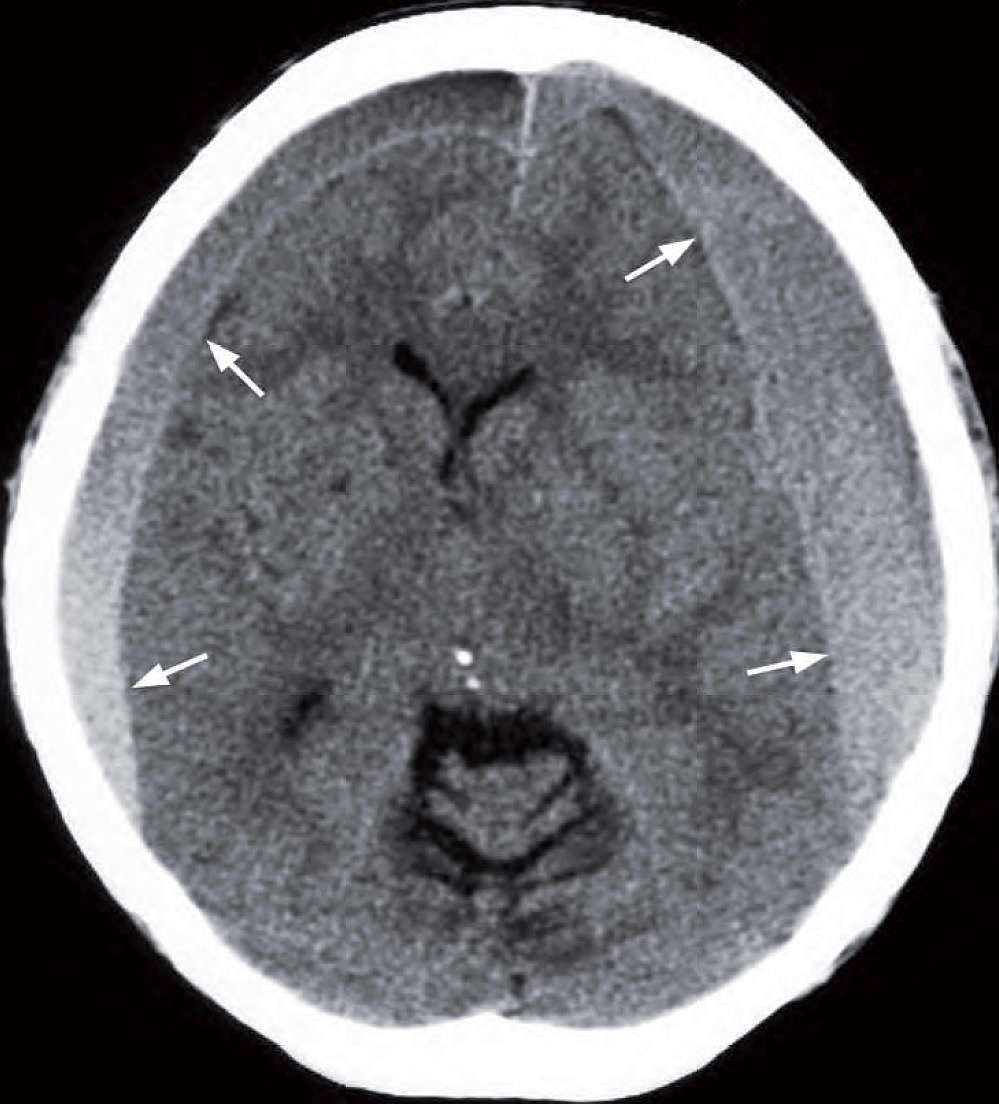

A 73-year-old woman presented with chronic headache, occasional vomiting, unsteadiness and frequent falls. In the past few months there had been a progressive deterioration in her mental function and increasing drowsiness. Physical examination showed moderate papilloedema but was otherwise unremarkable. A CT brain was performed.

What is shown on the CT and what is the diagnosis ?